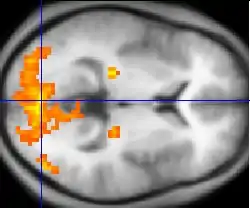

Functional MRI

Functional MRI (fMRI) measures signal changes in the brain that are due to changing neural activity. It is used to understand how different parts of the brain respond to external stimuli or passive activity in a resting state, and has applications in behavioral and cognitive research, and in planning neurosurgery of eloquent brain areas.[48][49] Researchers use statistical methods to construct a 3-D parametric map of the brain indicating the regions of the cortex that demonstrate a significant change in activity in response to the task. Compared to anatomical T1W imaging, the brain is scanned at lower spatial resolution but at a higher temporal resolution (typically once every 2–3 seconds). Increases in neural activity cause changes in the MR signal via T*

2 changes;[50] this mechanism is referred to as the BOLD (blood-oxygen-level dependent) effect. Increased neural activity causes an increased demand for oxygen, and the vascular system actually overcompensates for this, increasing the amount of oxygenated hemoglobin relative to deoxygenated hemoglobin. Because deoxygenated hemoglobin attenuates the MR signal, the vascular response leads to a signal increase that is related to the neural activity. The precise nature of the relationship between neural activity and the BOLD signal is a subject of current research. The BOLD effect also allows for the generation of high resolution 3D maps of the venous vasculature within neural tissue.

While BOLD signal analysis is the most common method employed for neuroscience studies in human subjects, the flexible nature of MR imaging provides means to sensitize the signal to other aspects of the blood supply. Alternative techniques employ arterial spin labeling (ASL) or weighting the MRI signal by cerebral blood flow (CBF) and cerebral blood volume (CBV). The CBV method requires injection of a class of MRI contrast agents that are now in human clinical trials. Because this method has been shown to be far more sensitive than the BOLD technique in preclinical studies, it may potentially expand the role of fMRI in clinical applications. The CBF method provides more quantitative information than the BOLD signal, albeit at a significant loss of detection sensitivity.